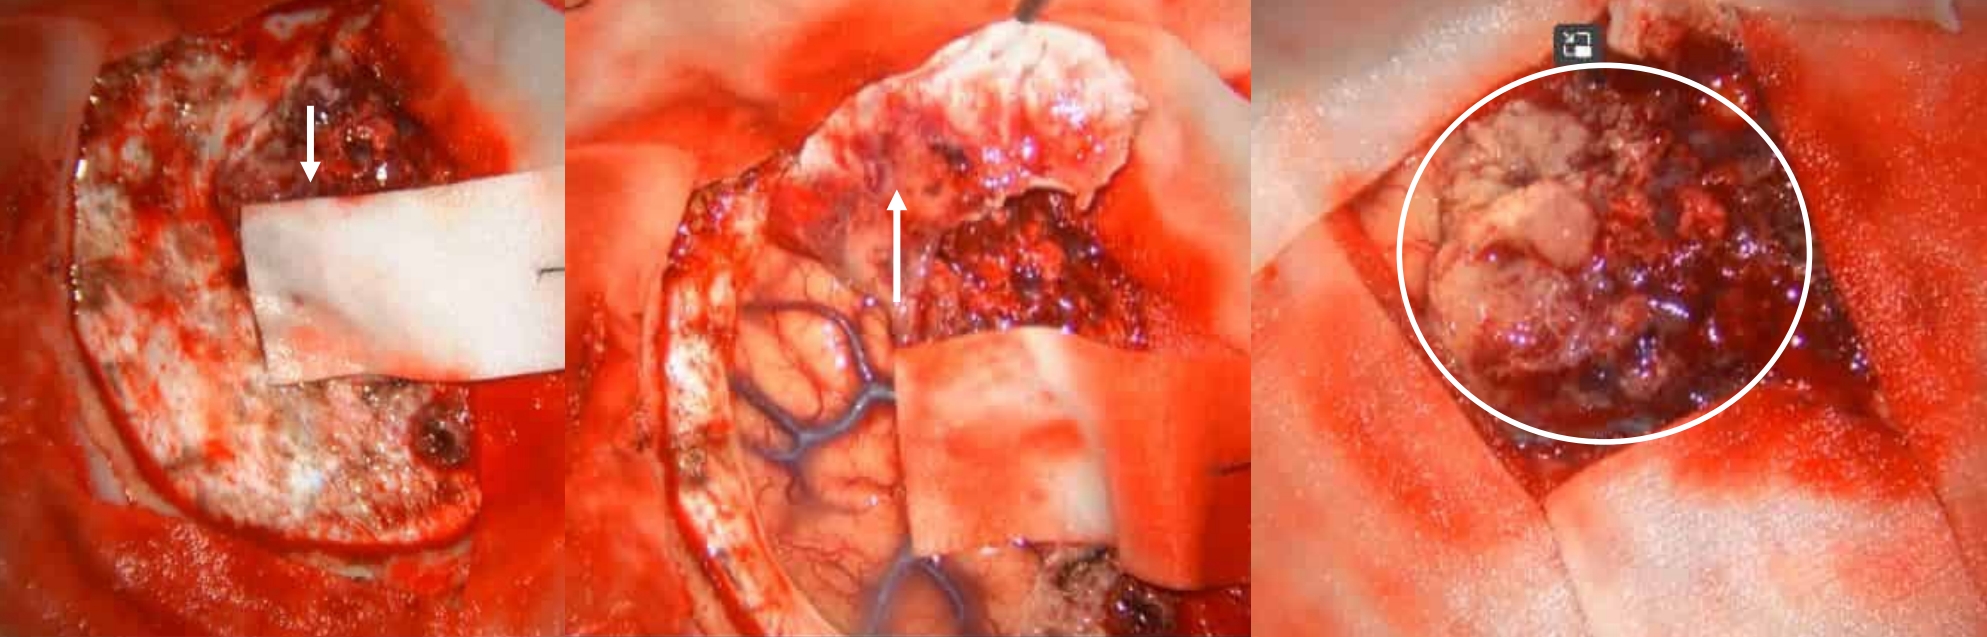

術中所見

腦膜瘤形態

①腫瘤已破壞硬膜

②腫瘤周圍腦膜尾征

③腫瘤

腦膜瘤完整切除

①腫瘤已累及大腦鐮

②切開大腦鐮檢查對側,避免漏切

③腫瘤全切,蛛網膜完整

顱骨全層受累病變

①顱骨內板增生

②顱骨外板受累

③顱骨全層增厚